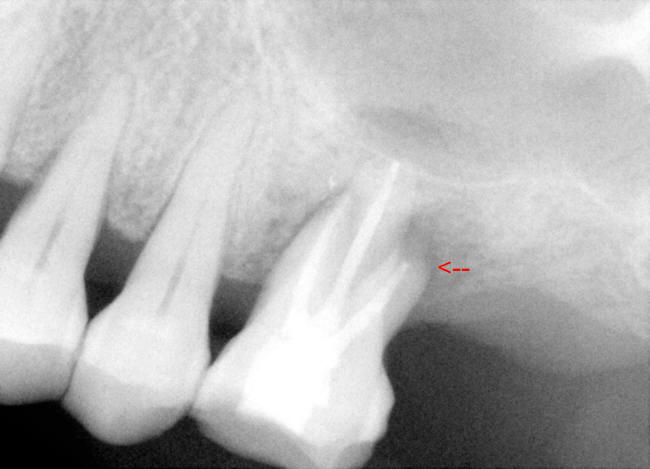

| 图三 术中根尖片插入主牙胶尖 | 图四 术中根尖片牙胶尖側方充填后 |

治疗:局麻,超声洁治4,5,6号牙,橡皮障隔离,开髓,活髓,使用特殊Piezo超声金刚钻头寻找MB2根管口,但是没有找到。使用根尖定位仪,用手用扩大针至15号,然后是用电动扩大针(Dentsply Tulsa Protaper),MB(近中根管),DB (远中根管)扩大到30/.06(锥度)14.5mm, P (鄂侧根管)40/.06 14.5mm,使用大量漂白液(sodium hypochlorite)冲洗和润滑剂,插入相应的主牙胶尖,拍摄根尖片(图三),距离尚可,P 根管最后通到 15mm,用纸尖吸干根管,介入AH Plus paste糊剂,再次插入相应的主牙胶尖,加入附加牙胶尖,侧方挤压充填,再次拍摄根尖片(图四),P根尖可能糊剂超充,去除多余牙胶尖,做轻度垂直挤压充填,使用Cavit暂时封闭根管治疗开口。治疗过程,林太太恶心两次,血压正常,自行好转。